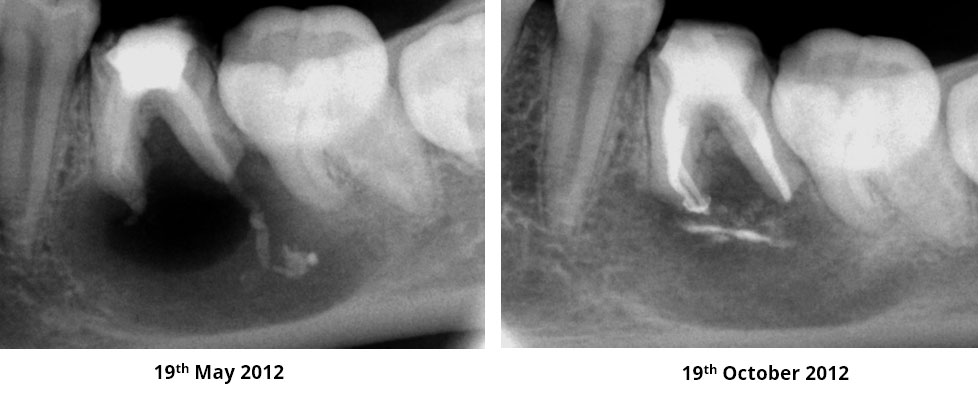

Age of patient: 15 years

Tooth: left mandibular first molar. Poor restorative prognosis. Very large lesion.

Work done: Obturation done after multiple calcium hydroxide dressings over 5 months and seeing lesion decrease in size. Fiber-post placed in distal canal. Core build-up done with Luxacore composite. Adv crown.

Notes: This is endo done for a “holding period” for implants later on. Healing of bone ensures a more favorable environment for implant placement.

Pre-op

Obturation done after 5 months of calcium hydroxide

May 2015 – 3 year recall

Pre-op & 3 year recall